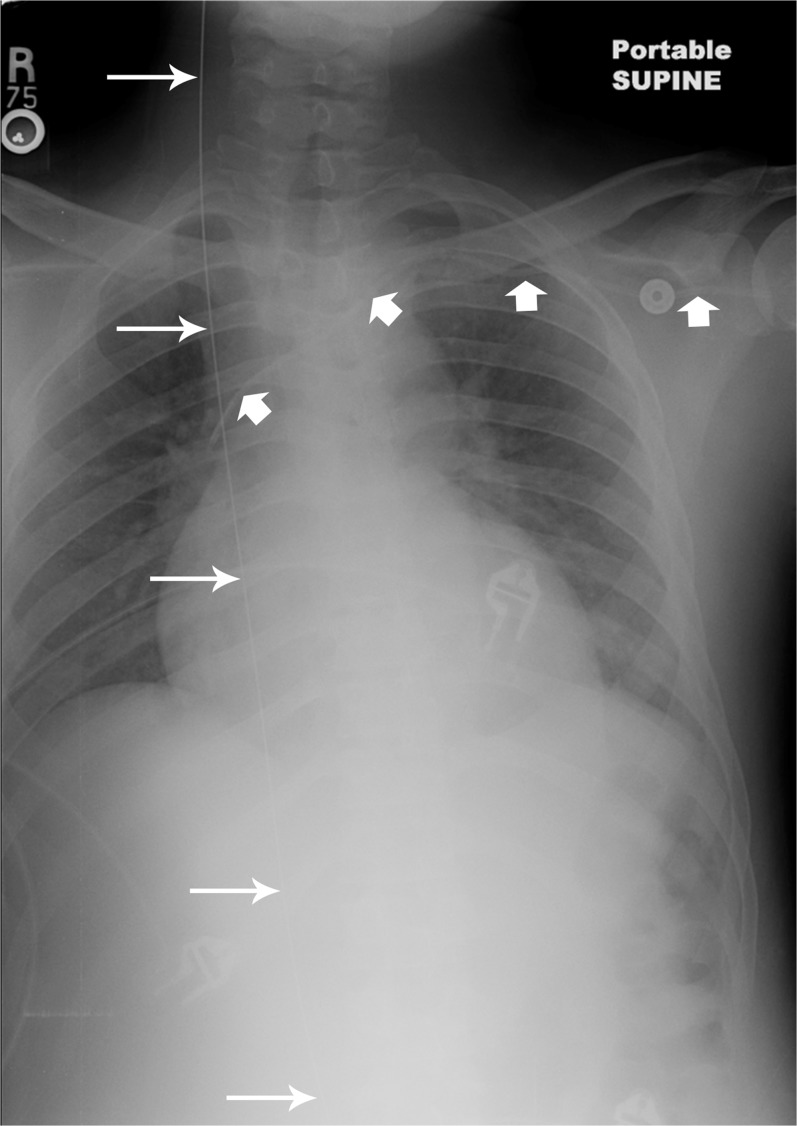

Figure 2.

Chest X-ray, with the retained guidewire in the inferior and superior vena cava ( thin arrows ) and left subclavian intravascular catheter ( thick arrows ).